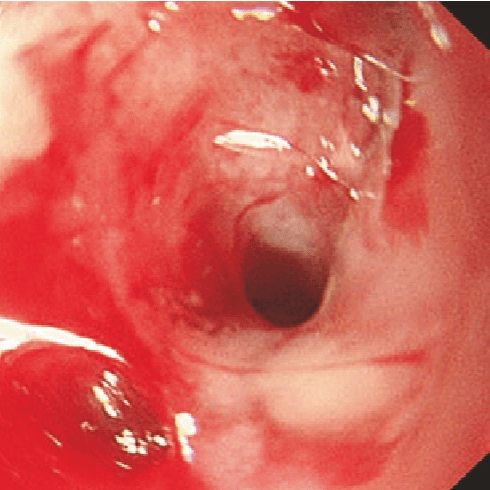

Rutgeerts i3

bolezn_krona.png

i3

Диффузный афтозный илеит с диффузно-воспаленной слизистой оболочкой